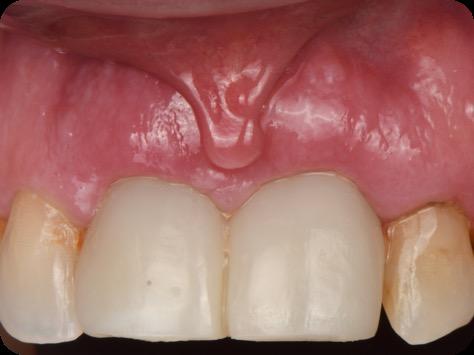

Fig 3. Provisional restorations on central incisors and gingival images. The gingival contours were optimal, and the gingival phenotype was thick.

Fig 16. Patient’s smile after implantation and previsualization